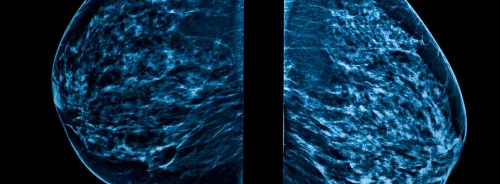

In a recent position paper published in the European Heart Journal the European Society of Cardiology (ESC) has urged cardiologists to reduce patient radiation exposure.

The paper outlines doses and risks of common cardiology examinations for the first time, and its lead author Dr Eugenio Picano, FESC, described cardiologists to be the ‘true contemporary radiologists’, as cardiology accounted for 40% of patient radiology exposure which equaled more than 50 chest X-rays per person per year.

Computed tomography (CT), percutaneous coronary intervention (PCI), cardiac electrophysiology and nuclear cardiology deliver a dose equivalent to 750 chest X-rays (with wide variation from 100 to 2,000 chest X-rays) per procedure.